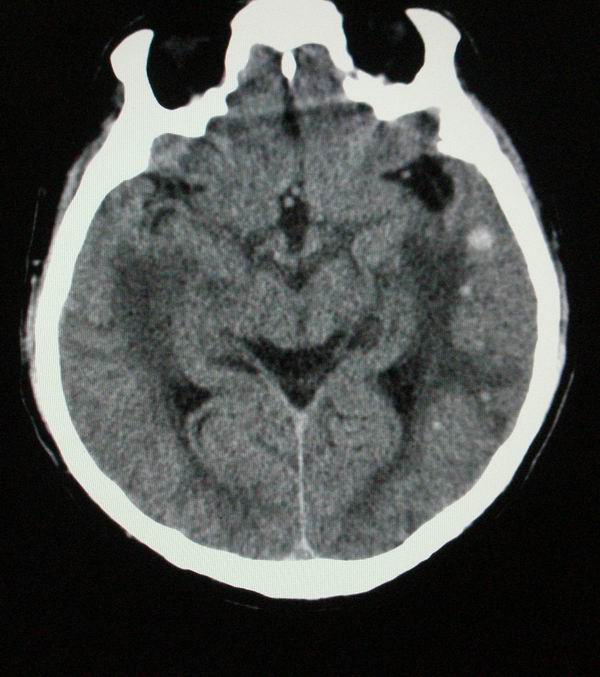

以下是引用随光逐影在2008-4-5 7:46:00的发言:[br]1)考虑为:多发性脑转移瘤。建议:行进一步检查。2)多发性腔隙性脑梗塞。3)脑白质病。4)脑萎缩。

以下是引用zjzjr在2008-4-5 9:00:00的发言:[br]1.双侧颞叶占位性病变,考虑为转移瘤可能性大。[br]2.左侧基底节区陈旧性腔隙性脑梗塞。[br]3.脑白质病。建议mri进一步检查。

以下是引用xuhuihong在2008-4-5 0:59:00的发言:[br]1.双侧颞叶占位性病变,考虑为转移瘤可能性大。[br]2.左侧基底节区陈旧性腔隙性脑梗塞。[br]3.脑白质病。建议mri进一步检查。

以下是引用形影不离在2008-4-4 23:29:00的发言:[br]1.双侧颞叶占位性病变,考虑为转移瘤可能性大。[br]2.左侧基底节区陈旧性腔隙性脑梗塞。[br]3.脑白质病。